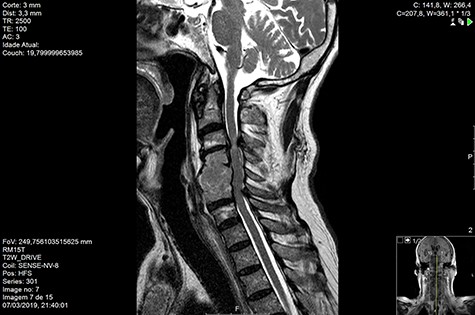

Computed tomography (CT) (Figs 1–3) and magnetic resonance imaging (MRI) (Figs 4–6) of the cervical spine were performed and revealed a lytic lesion involving most of C4, C5 and C6 vertebral bodies with bilateral extension to the posterior spinal elements of C4 and C5 and complete disruption of C4-C5 and C5-C6 intervertebral discs.

The Spinal Instability Neoplastic Score (SINS) [4, 6, 7] for assessing spinal instability from metastatic disease was used and the lesion was deemed unstable (SINS 13), with impending risk of increased neurological damage.

MRI and CT scans performed at 90 days post-radiation therapy showed an arrest of further progression of instability and resolution of the lytic lesion (Figs 7–13).